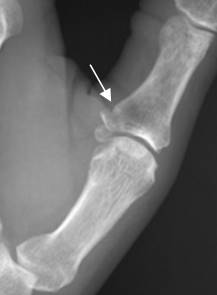

Fig 185. Fractura del esquiador.

A: Rx AP y B: Rx lateral del pulgar. Fractura en la base de la falange proximal del 1 dedo.